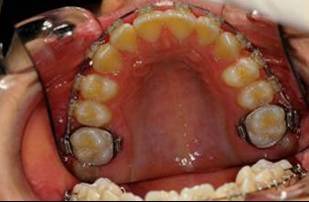

En fouillant dans mes cas j'ai trouve celui ci qui presente une beance assez importante. Je me suis rappele qu'un certain message etait lance il y a qq temps a propos d'un enfant qui presente une beance et de savoire comment faire dans ce cas. Je pense qu'il est interessant de voir comment les uns et les autres prennent en charge ce type de cas. Il s'agit d'un fille de 12 ans, succion de pouce, interposition linguale totale, beance de molaire a molaire, respiration mixte, incompetence labiale au repos, fonction labiale serree. Le total quoi!!! Voici la premiere serie de photos

la suite de documents, comme vous allez le voir le premier moyen est un qh, mais quelle sera la suite?

1- RDV 1: QH

2- RDV 2 : Commencer avec ecran buccal + exercice de respiration

3- Quant elle est capable de garder oral screen toute la nuit je considere que la batail est gagnee

4- Collage de l'arcade sup, presque 6 mois apres et voici le photo apres seance de college